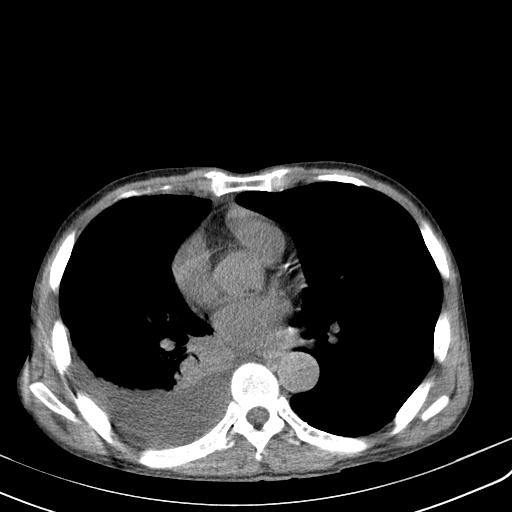

男性 75  咳嗽 一周前发热最高达39

右肺继发型tb并右侧tb性胸腔炎,右侧胸腔大量积液并右下肺膨胀不全,慢支肺气肿、多发肺大泡。建议抽胸水实验室检查并复查排除恶性在占位。

右上肺继发型肺结核,右胸腔中等量积液。

左上肺大泡。

结核的基础上有纵隔淋巴结肿大,右侧有胸水,但右侧纵隔反而窄,说明有肺有不张。

再就是右下肺有块影,和不张混合,还是不能除外肺癌。

补充材料,患者2月份ct片大致正常,双侧胸腔积液,2月份抽胸水未发现ca细胞,现患者发热,痰多,各气管通畅,

1)右肺继发型肺结核。2)左肺胸膜下多发性肺大泡。3)右侧胸腔积液。